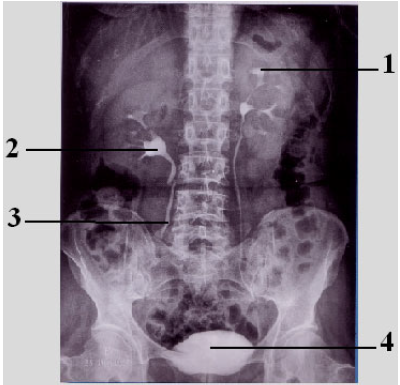

Observe a figura abaixo e, após, responda à questão.

Identifique as estruturas anatômicas assinaladas na figura e assinale a alternativa correta.

Observe a figura abaixo e assinale a alternativa que apresenta a sequência correta das estruturas assinaladas.